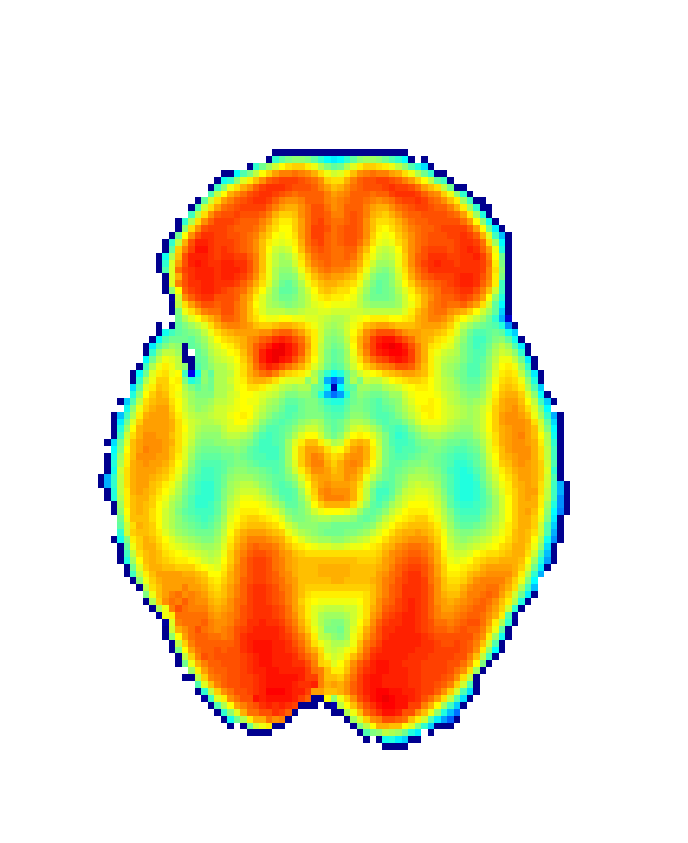

First, images used in biomedical studies are often irregularly shaped, which implies a need for reliable smoothing methods. However, such methods usually suffer from a problem of leakage with complex data structures such as the ones here considered, showing difficulties in the estimation for boundary regions. With our FDA approach, this problem is addressed by applying bivariate splines over Delaunay triangulations [61], thus preserving the features of these complex brain images [62] (see Figure 3).

Refer to caption

(a) N=8

(b) N=15

(c) N=25

Figure 3: Delaunay triangulations for SCCs construction at Z=30𝑍30Z=30. Increasing N values represent increases in triangulation’s degree of fineness. Wang et al. [63] consider a fineness degree of N=8 as sufficient.